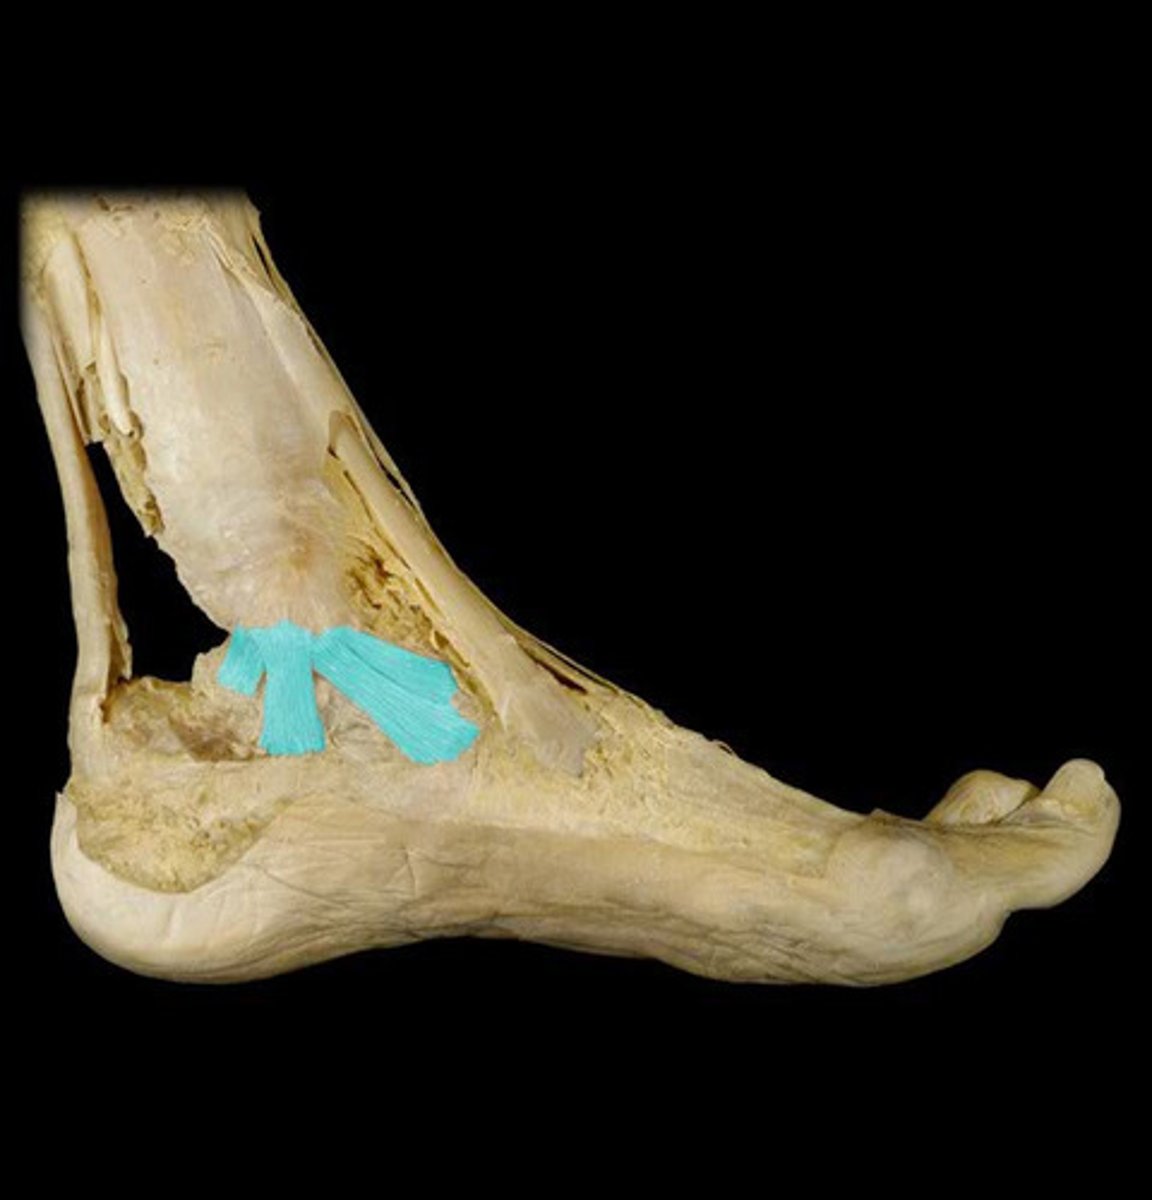

Components of the deltoid ligament (3)

Tibionavicular fibers

Tibiocalcaneal fibers

Tibiotalar fibers

Function of the deltoid ligament (I function, 3 joints)

Limits eversion at the:

Talocrural joint

Subtalar joint

Talonavicular joint

Why does the deltoid ligament have a lower injury rate than the lateral ankle ligaments? (2 reasons)

Higher strength of deltoid ligaments

Lateral malleolus blocks excessive eversion